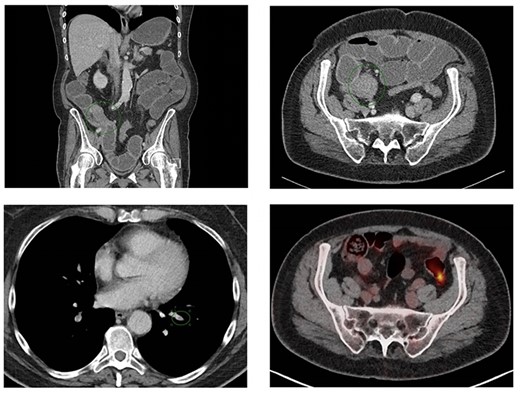

(A) Axial slice of a thoracic PET/CT showing the lobular carcinoma in the left mamma (green arrow) before neoadjuvant chemotherapy. This PET/CT was performed 7 months prior to ER presentation. (B) Axial slice of a thoracic PET/CT showing the lobular carcinoma in the left mamma (green arrow) after neoadjuvant chemotherapy with partial response. This PET/CT was performed 7 weeks prior to ER presentation.